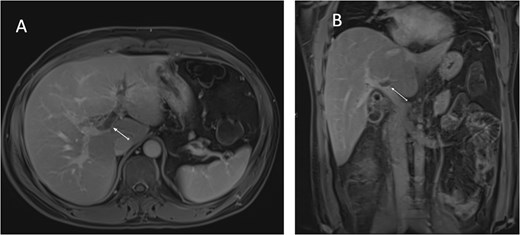

An ultrasound of the abdomen showed an impacted stone at the neck of the gallbladder with acute cholecystitis. The patient was admitted and started on IV antibiotics. He developed tachycardia reaching 110 bpm and had a high white blood cell count; therefore, the decision was made to proceed with a contrast-enhanced computed tomography (CT) scan, which showed evidence of acute cholecystitis and left PVT (Fig. 1). The medical team was consulted, and IV heparin without bolus was started. The gastroenterology team was consulted for his high bilirubin levels and advised for magnetic resonance cholangiopancreatography (MRCP), which was done the next day and confirmed the findings of left PVT (Fig. 2). MRCP also showed a micro perforation of the gallbladder and no biliary obstruction or stones (Fig. 3).

Contrast-enhanced CT scan of the abdomen: (A) axial cut; (B) coronal cut. Arrow indicates left portal vein thrombosis.